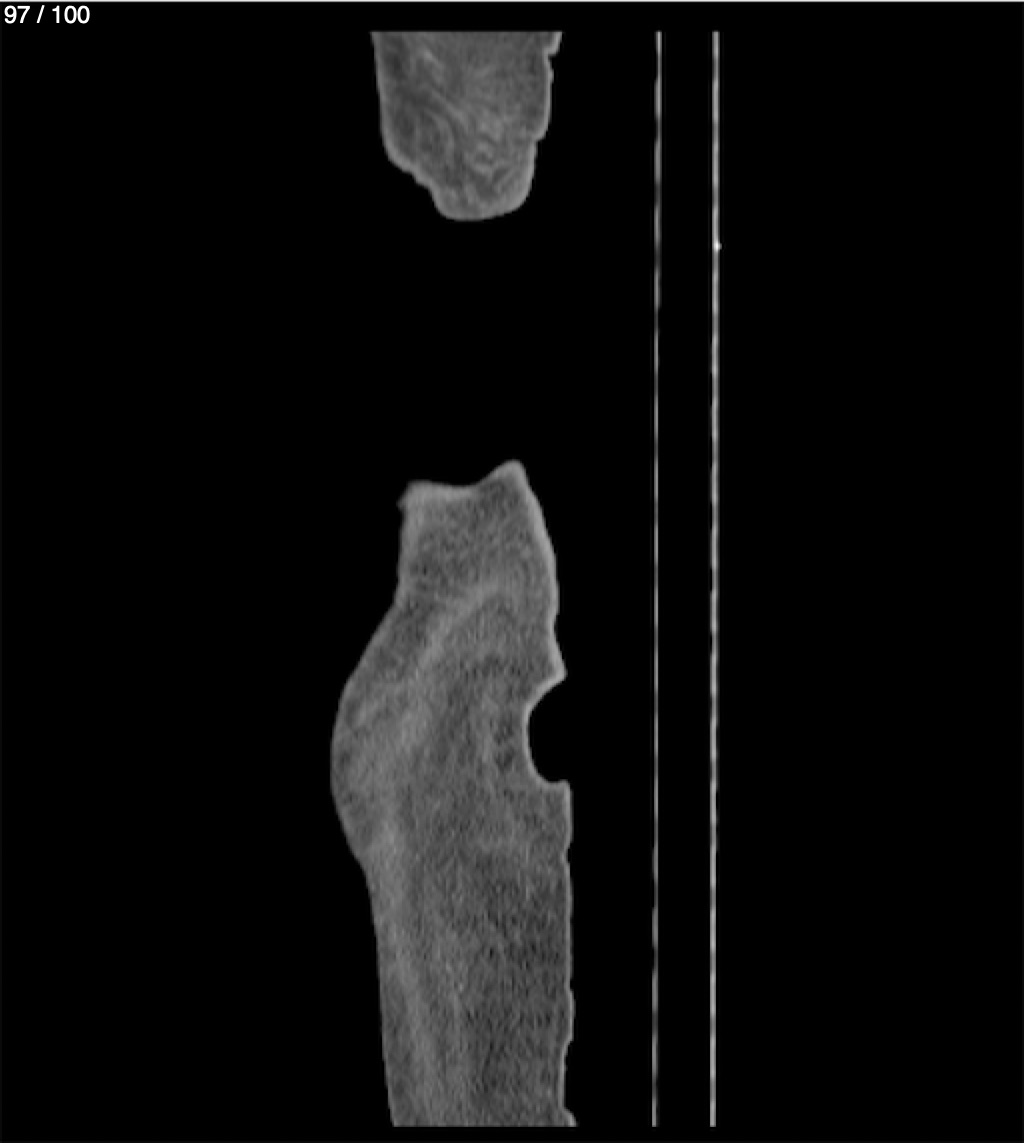

Hilda Geronimo Mendez 60A - T.C Abdomen Simple